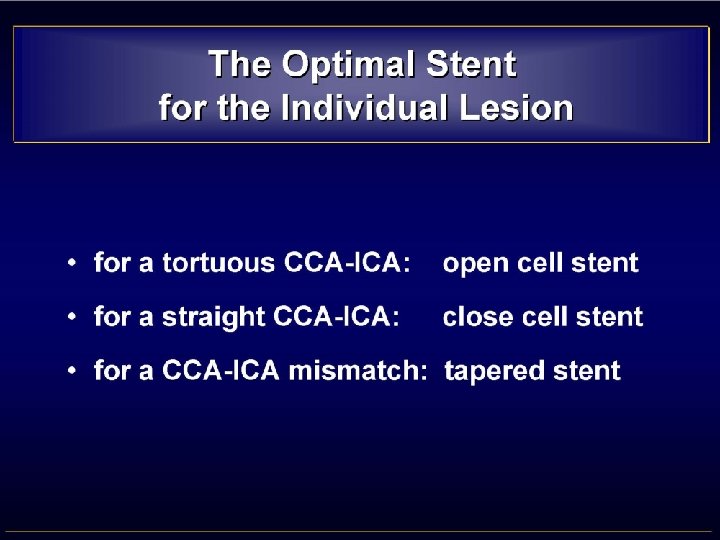

• MISMATCH CCA-ICA